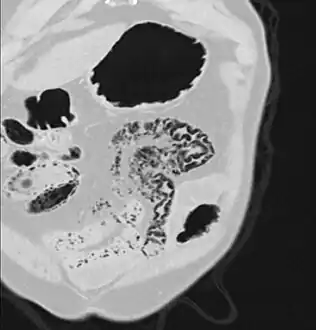

Pneumatosis intestinalis at computed tomography in intestinal ischemia. Lung window for better representation of the gas deposits in the intestinal walls. Coronal reconstruction.

Pneumatosis intestinalis in the coronal computed tomography in lung window. It can be seen next to gas entrapment in the bowel wall and gas in the stomach wall and in numerous vessels, including the portal vein into the liver.